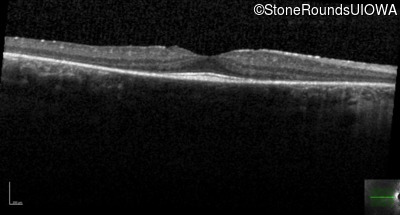

Age at visit: 19 years (Visit 2)

The clinical features favoring the diagnosis of retinitis pigmentosa with anisocytosis include: childhood onset periodic fever; mild anemia; anisocytosis on peripheral blood smear; night blindness and constricted visual fields as his earliest visual symptoms; bone-spicule-like pigmentation and narrowed arterioles on fundus examination; loss of outer retinal structures on OCT; and, normally sighted parents.